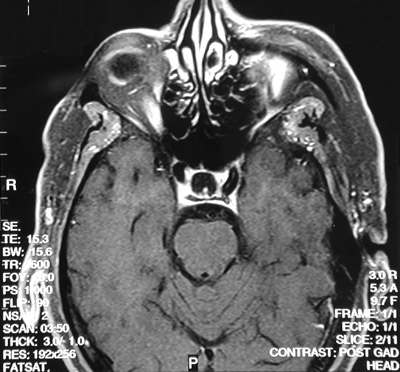

![]() | The FSE T2 weighted MRI scan in axial view above demonstrates bright fluid filling the sella turcica, indicative of an empty sella syndrdome. In the T1 weighted post gadolinium view below the sella appears dark. This peculiar syndrome can lead to hypopituitarism. |